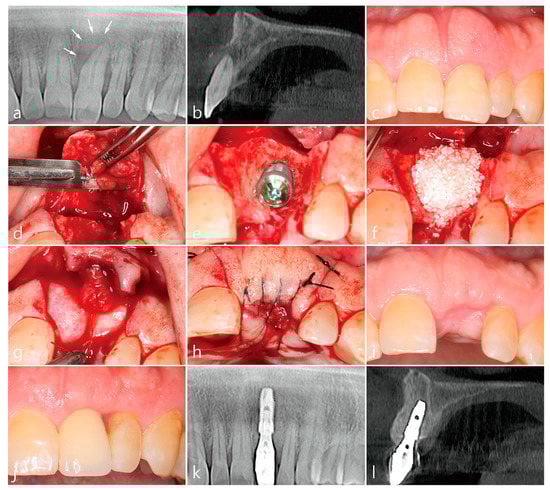

5. Case 3

- A tooth or implant with severe bone loss was removed using extraction forceps under local anesthesia with 2% lidocaine containing 1:100,000 epinephrine;

- A midcrestal incision and two buccal vertical incisions were made. Before raising the flap, special care was taken to ensure a clean dissection of the IGT from the underlying flap without any damage and the IGT is still well-attached to the flap. The IGT was then further separated from the bony housing by using a curette with various curvatures and a periosteal elevator.

- The IGT attached to the buccal flap was dissected to an appropriate thickness using a #15 blade so that the base of the IGT was still attached to the existing flap, and the flap was eventually extended. Periosteal releasing incisions were not performed at the flap base.

- The extraction socket was thoroughly debrided using a Molt curette and a titanium brush.

- A surgical guided stent was used so that the implant (Implantium, Dentium, Suwon, Korea) was placed 2.0 mm subcrestal to the level of the adjacent bone in the extraction socket.

- A synthetic osteoconductive bone graft substitute composed of hydroxyapatite (HA) and beta-Tricalcium phosphate (β-TCP) (Osteon III, Genoss, Suwon, Korea) and a resorbable collagen membrane (Genoss, Suwon, Korea) were placed to cover the implant and the peri-implant osseous defect.

- After covering the bone graft with the collagen membrane, the extended IGT was sutured with the palatal flap with 4-0 Catgut. Next, the buccal flap was closed using 4-0 nylon or black silk.

- Uncovering procedures were performed 4–6 months after initial surgery. Under local anesthesia, the buccal flap was reflected, the regenerated tissue above the implant cover screw was removed, and the healing abutment was connected to the implant. The buccal flap was closed using 4-0 Catgut or black silk. Antibiotics and anti-inflammatory drugs were prescribed for 5 days. The prosthesis was installed 2 months after uncovering.